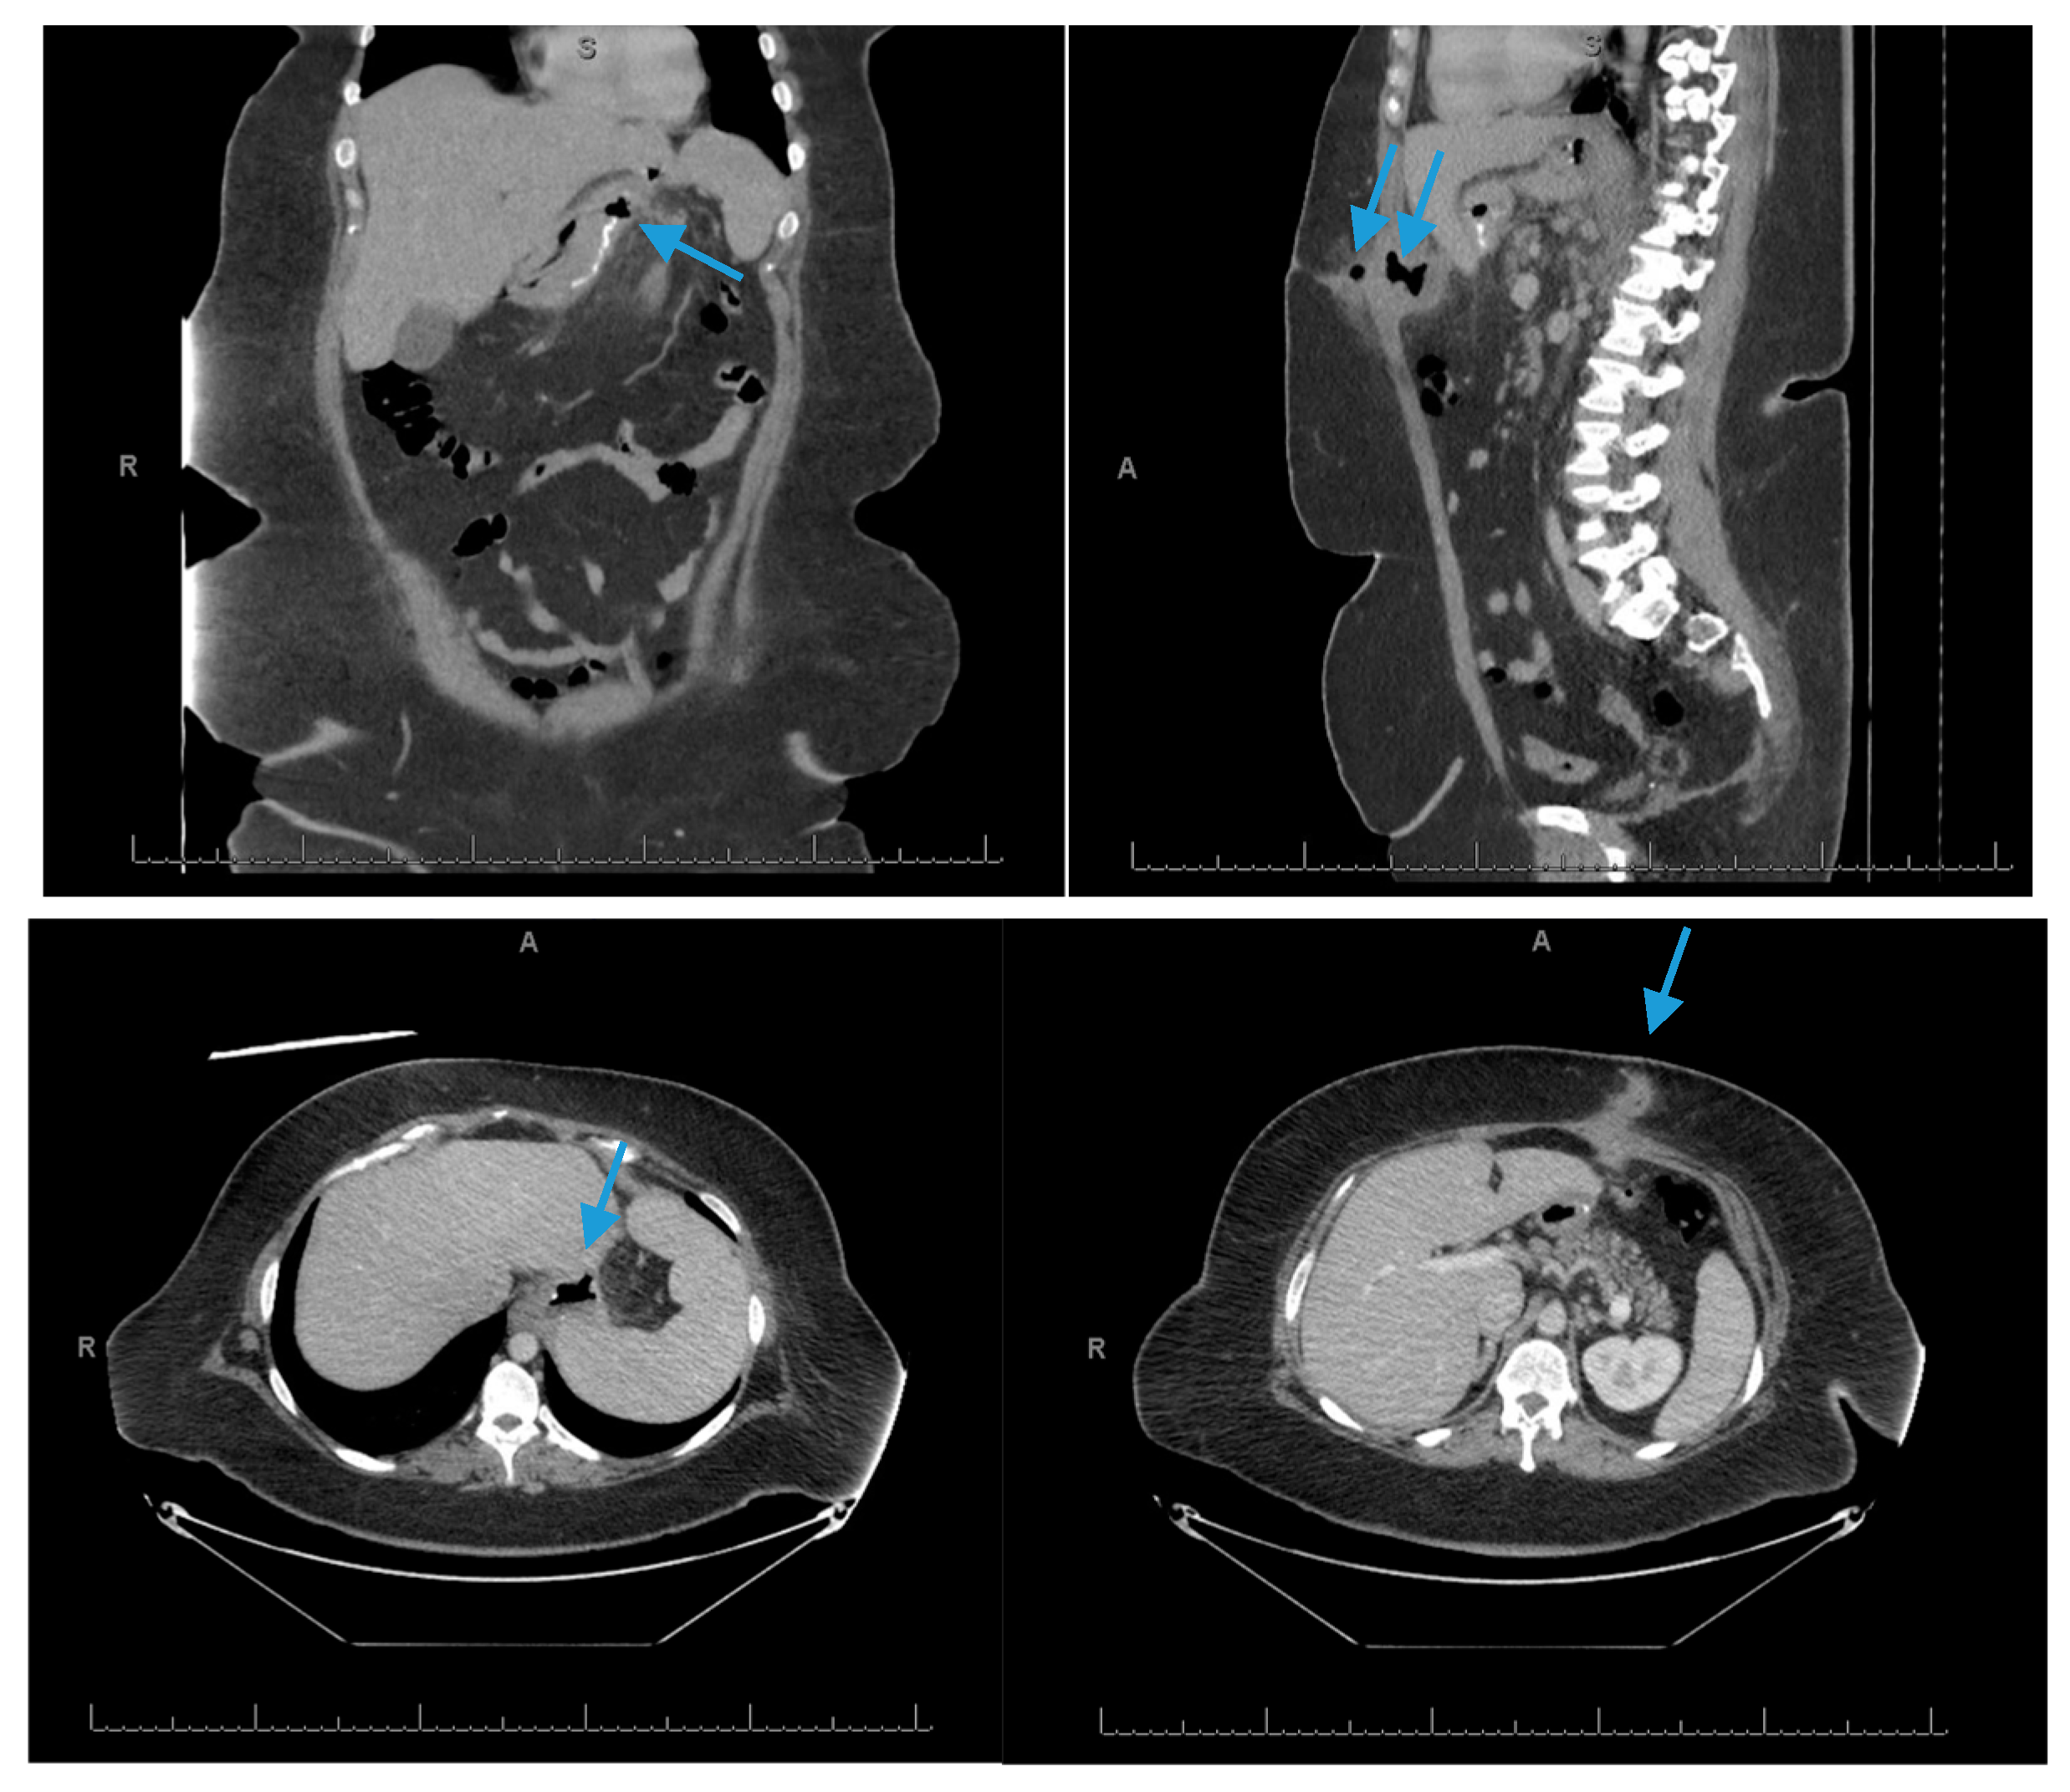

3.2. Endoscopic Stenting